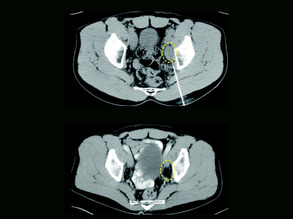

Cycling and Cancer